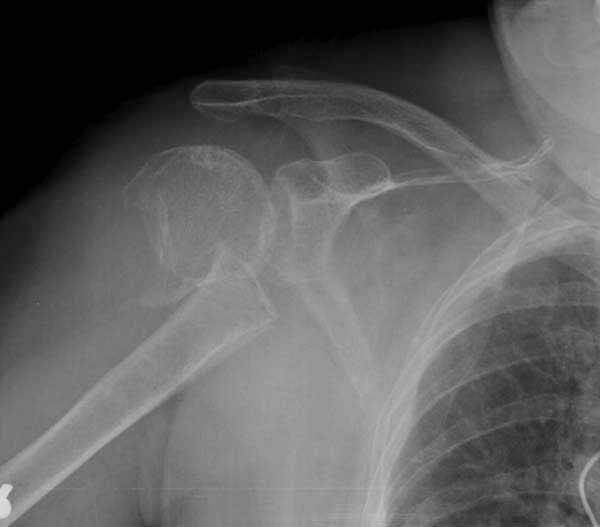

Уважаемы коллеги! Прошу помочь определиться с тактикой лечения пациентки. В феврале в отделение поступила пациентка с оскольчатым переломо-вывихом головки плечевой кости. Выполнена операция -остеосинтез блокируемой пластиной. Костная пластика не производилась. На контрольных рентгенограммах остается сублюксация головки и смещение большого бугорка. Интраоперационно бугорок подшивался с помощью лавсановых нитей. Послеоперационно: ношение косыночной повязки и пассивные движения в плечевом суставе в течение 2,5-х месяцев без особенностей. Через 2,5 месяца при попытке выполнения пассивно-активных движений произошел передний вывих плечевой кости.Вся реабилитация производилась по месту жительства. Таким образом существование вывиха в течение 1 месяца. Боли не беспокоят. Нейрососудистых нарушений в конечности нет. Что вы можете посоветовать: пластику, эндопротез, артродез? Заранее спасибо.

мне кажется ,что на послеоперационном снимке, также имеется сублюксация головки.сколько годов пациентке?

Уважаемый коллега. На мой взгляд имеющаяся дислокация головки обусловлена на мой взгляд имеющейся у пациента обширной травмой ротаторного аппарата. В пользу данной точки зрения могу привести следующее: на представленных Вами рентгенограммах хорошо заметен отрыв большого бугорка со смещением отломков который как известно является точкой прикрепления коротких наружных ротаторов плеча. Последующая миграция данного фрагмента и неполноценная репозиция его при первичном остеосинтезе с нестабильной фиксацией на мой взгляд и обусловили создавшуюся ситуацию. то что пациента не беспокоят боли позволю подвергнуть сомнению поскольку сам занимаюсь хирургией плеча и с подобными ситуациями сталкивался неоднократно. На мой взгляд в настоящее время целесообразно проведение повторного оперативного вмешательства с адекватным восстановлением ротаторного аппарата, поскольку дальнейшее затягивание сложившейся ситуации уменьшает шанс на успех данного вмешательства.

Набор мелких снимков не отражает истинную картину суставной поверхности лопатки, а также качество репозиции головки плеча. Необходимо доказать аксиальным снимком наличие покрытия головки. Правильная маркировка на рентген снимках и соответствие с выставленным диагнозом гарантирует от ошибок со стороной во время операции!